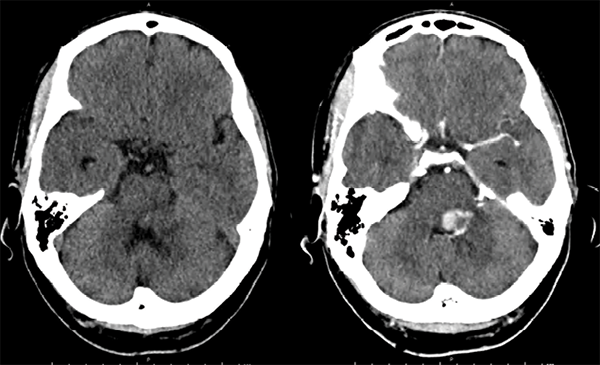

La tomografía computada (TC) de encéfalo reveló una imagen hipodensa a nivel protuberancial (Fig. 1) caracterizada mejor en resonancia magnética (RM) donde se observó en topografía tronco encefálica a nivel protuberancial medial y paramedial izquierda la presencia de una lesión expansiva que deforma el contorno anterior del cuarto ventrículo y se proyecta sobre el pedúnculo cerebeloso medio (Fig. 2). La lesión genera efecto de masa del sector, presenta naturaleza sólida, señal de resonancia heterogénea en su interior, contornos parcialmente definidos con un diámetro longitudinal de 14 mm, diámetro transversal de 17 mm y diámetro anteroposterior de 16 mm. La lesión es hiperintensa y heterogénea en secuencia T2 y FLAIR e hipointensa en T1, con edema perilesional tal cual son puestos de manifiesto en la imagen T2 coronal, que involucran la protuberancia y el mesencéfalo izquierdo. La lesión ocupante de espacio no mostró netarestricción en las secuencias moleculares de Difusión y ADC. No mostró cambios en la señal en la secuencia T2-GRE (Fig. 2).

Fig. 1. Tomografía preoperatoria; A: sin contraste. B: con contraste